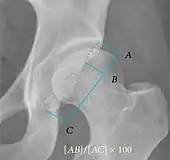

| Crossing ratio | ![]() |

Percentage of acetabular walls crossing. Normal acetabulum is oriented in anteversion. Its value ranges from 15 to 20° in the equatorial plane of the acetabulum and decreases gradually towards the acetabular roof, where normal values range from 0 to 5°. Retroversion of the upper part of the acetabulum has been related with pincer type impingement. In radiography the presence of a "crossover sign" is produced when the posterior wall of the acetabulum crosses the anterior wall before reaching the acetabular roof. It is a sign of acetabular retroversion and it has been linked with overcoverage and pincer impingement. Nevertheless, this sign has been described in 6% of the normal population. Therefore, more important than its presence is the percentage of crossing. | <20%